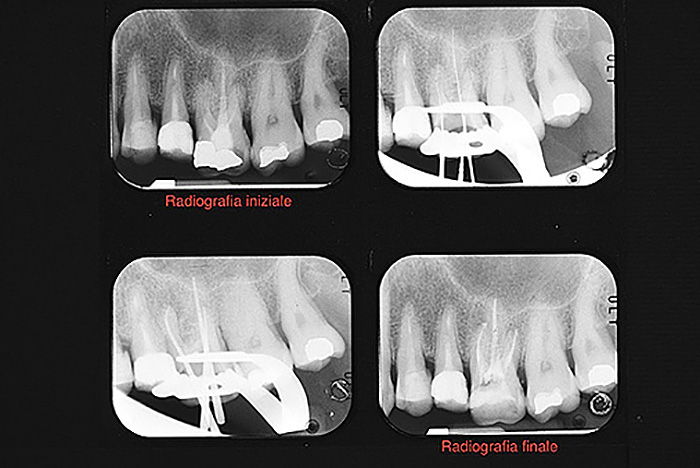

La prima fase della terapia è la corretta esecuzione di una radiografia diagnostica/preoperatoria al fine di ottenere tutte le informazioni sull’anatomia del dente in esame, successivamente si deve isolare il dente con la diga di gomma; è questo un presidio indispensabile per l’esecuzione di una corretta terapia il cui obiettivo è quello di disinfettare e detergere un sistema canalare (endodonto), e dunque il primo passo da fare è quello di evitare di contaminarlo ulteriormente con i batteri di cui la saliva è ricca. Il dente isolato con la diga di gomma è infatti completamente separato dal resto della bocca, garantendo un’ottimale detersione chimica da un lato e preservando il paziente dalla involontaria ingestione di disinfettanti o strumentario.

E’ molto importante monitorare nel tempo il ritrattamento, eseguendo radiografie di controllo a distanza che documenteranno le modificazioni morfologiche della lesione periapicale e consentiranno al clinico di pronunciarsi in merito alla guarigione e alla prognosi del singolo caso.